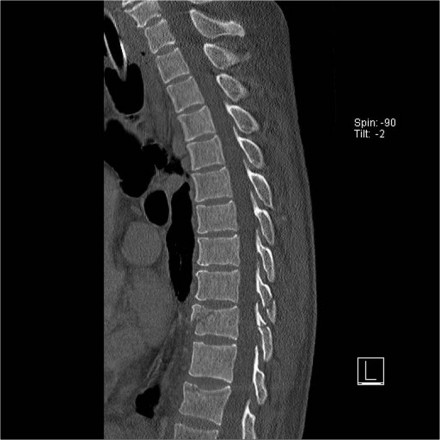

Here is a patient with distraction on the anterior side.

Notice the rigid spine and how easily this major injury can be overlooked.

This patient had a motorcycle accident.

The MRI demonstrates rupture of the flava ligaments, interspinous and supraspinous ligaments as well as fracture of the posterior elements and compression of the vertebral body.

A posterior spondylodesis was performed.